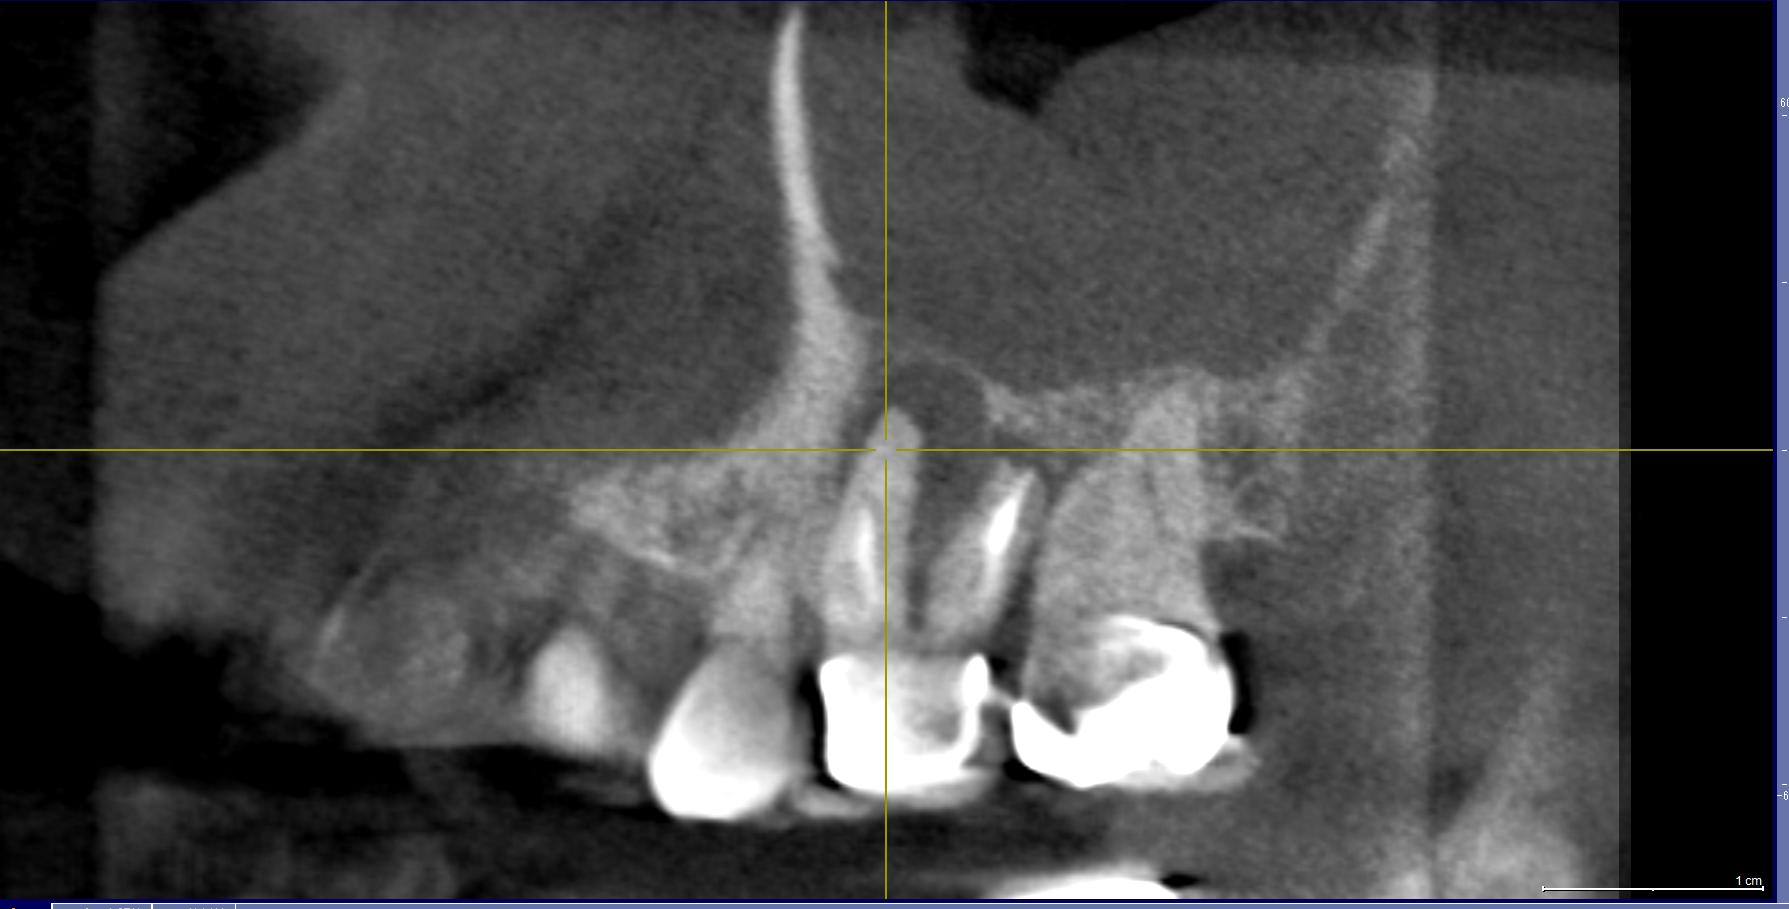

CT:重症の虫歯が根管を超え鼻の部屋に入っていました。鼻から変な汁もでる状況。皆さん歯科ドックではここまでわかります。必ず精密検査をお勧めします。骨にも穴が開いている。。。。

シンプルにいくなら抜歯。かなと。これはもし残すなら精密根管治療が必要ですがCTを見ると根管が狭窄(詰まっている)して器具が貫通できない可能性が高いのです。

やはり膿が!!感染源が。そして肝心の根管がやはりCTで見た通り狭窄。通らない。

今日ダメだったらやめましょう。そう伝えCTを術前に撮影。

鼻の部屋の病気が引いていました!!嬉しい。治癒傾向は間違いがない。ただ治癒だけではだめだ。根治だと自分に言い聞かせ昼休みを使ってゆっくり丁寧にマイクロスコープで根管を探りました。

根尖見えますね。根管を綺麗にして。次回根充(MTA)予定です。時間がかかったけど本当に良かったです。お付き合いいただいたMさんに感謝!!